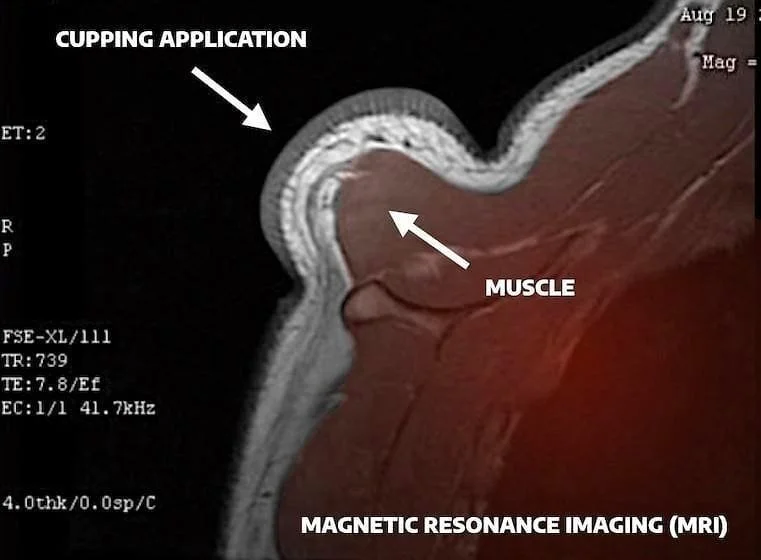

effects of cupping under MRI

MRI of what happens during cupping. Picture credit to @Cuptherapy

MRI studies have shown that cupping therapy creates lasting space within the body’s internal structures, not just during treatment but even after the cups are removed (see picture below).

By gently lifting the skin and underlying tissues, cupping increases volume within the fascia, reducing mechanical stress and stimulating the nervous system. This process promotes decompression, improves circulation, enhances mobility, and supports the body’s natural healing response.